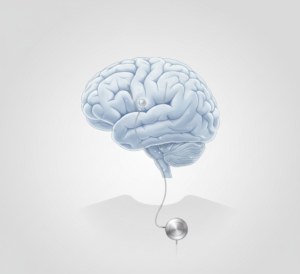

Beynin hedeflenen bölgelerine ince elektrotlar yerleştirilir ve bu elektrotlar cilt altına yerleştirilen küçük bir uyarı cihazına bağlanır. Uyarı ayarları hekimler tarafından yapılır ve takip süreçlerinde düzenlenebilir.

Beyin Pili Ayarlama ve Takip

Beyin pili takılan hastalarda, cihaz ayarlarının düzenlenmesi ve tedavi takibi planlı kontrollerle yapılır. Ayarlar, hastanın klinik durumuna göre hekim tarafından belirlenir.